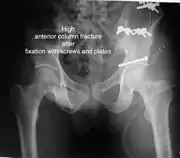

High anterior column fracture 3 D CT scan picture

High anterior column fracture after fixation with screws and plates

The final management depends on the size of the fragment(s), stability and congruence of the joint. In some cases traction for six to eight weeks may be the only treatment required; however, surgical fixation using screw(s) and plate(s) may be required if the injury is more complex. The latter treatment will be called for if bone fragments do not fall into place, or if they are found in the joint, or if the joint itself is unstable.